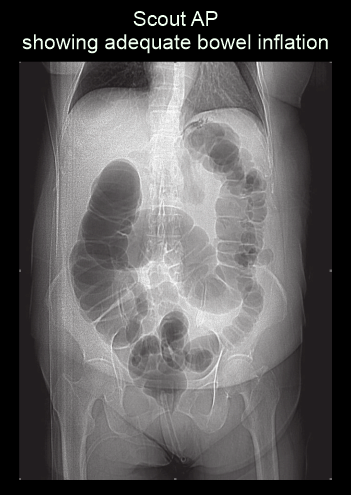

- Turn in to supine position after achieving a full colon distension, and perform a scout view toconfirm.

Scan planning

- Plan the scan slab to cover from the dome of the diaphragm to a level just below the ischial tuberosities.

Explanation: to completely cover both colon and rectum.